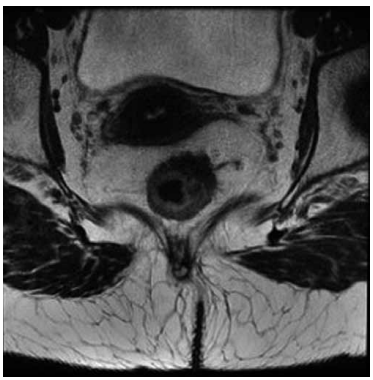

Paciente de 65 anos, sexo masculino, apresenta quadro

clínico de tenesmo e sangramento após evacuação. Realizada colonoscopia, e identificada lesão em reto médio,

que se estende de 7 a 10 cm da borda anal (adenocarcinoma).

A ressonância magnética de pelve do paciente caracteriza estadiamento clínico T3bN0:

(Arquivo pessoal; imagem utilizada com autorização)

Foram descartadas metástases a distância. Assinale a alternativa correta a respeito do caso.